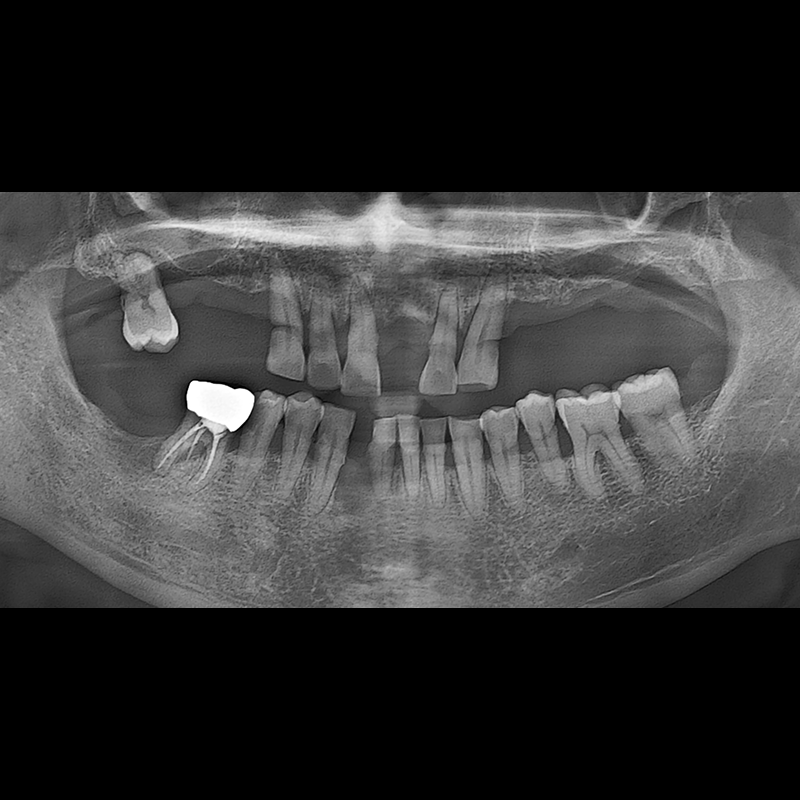

BEFORE AFTER

インプラント手術事例 2025.05.30

欠損した歯の部分と、生かしにくい歯の位置にインプラントを植立しました。